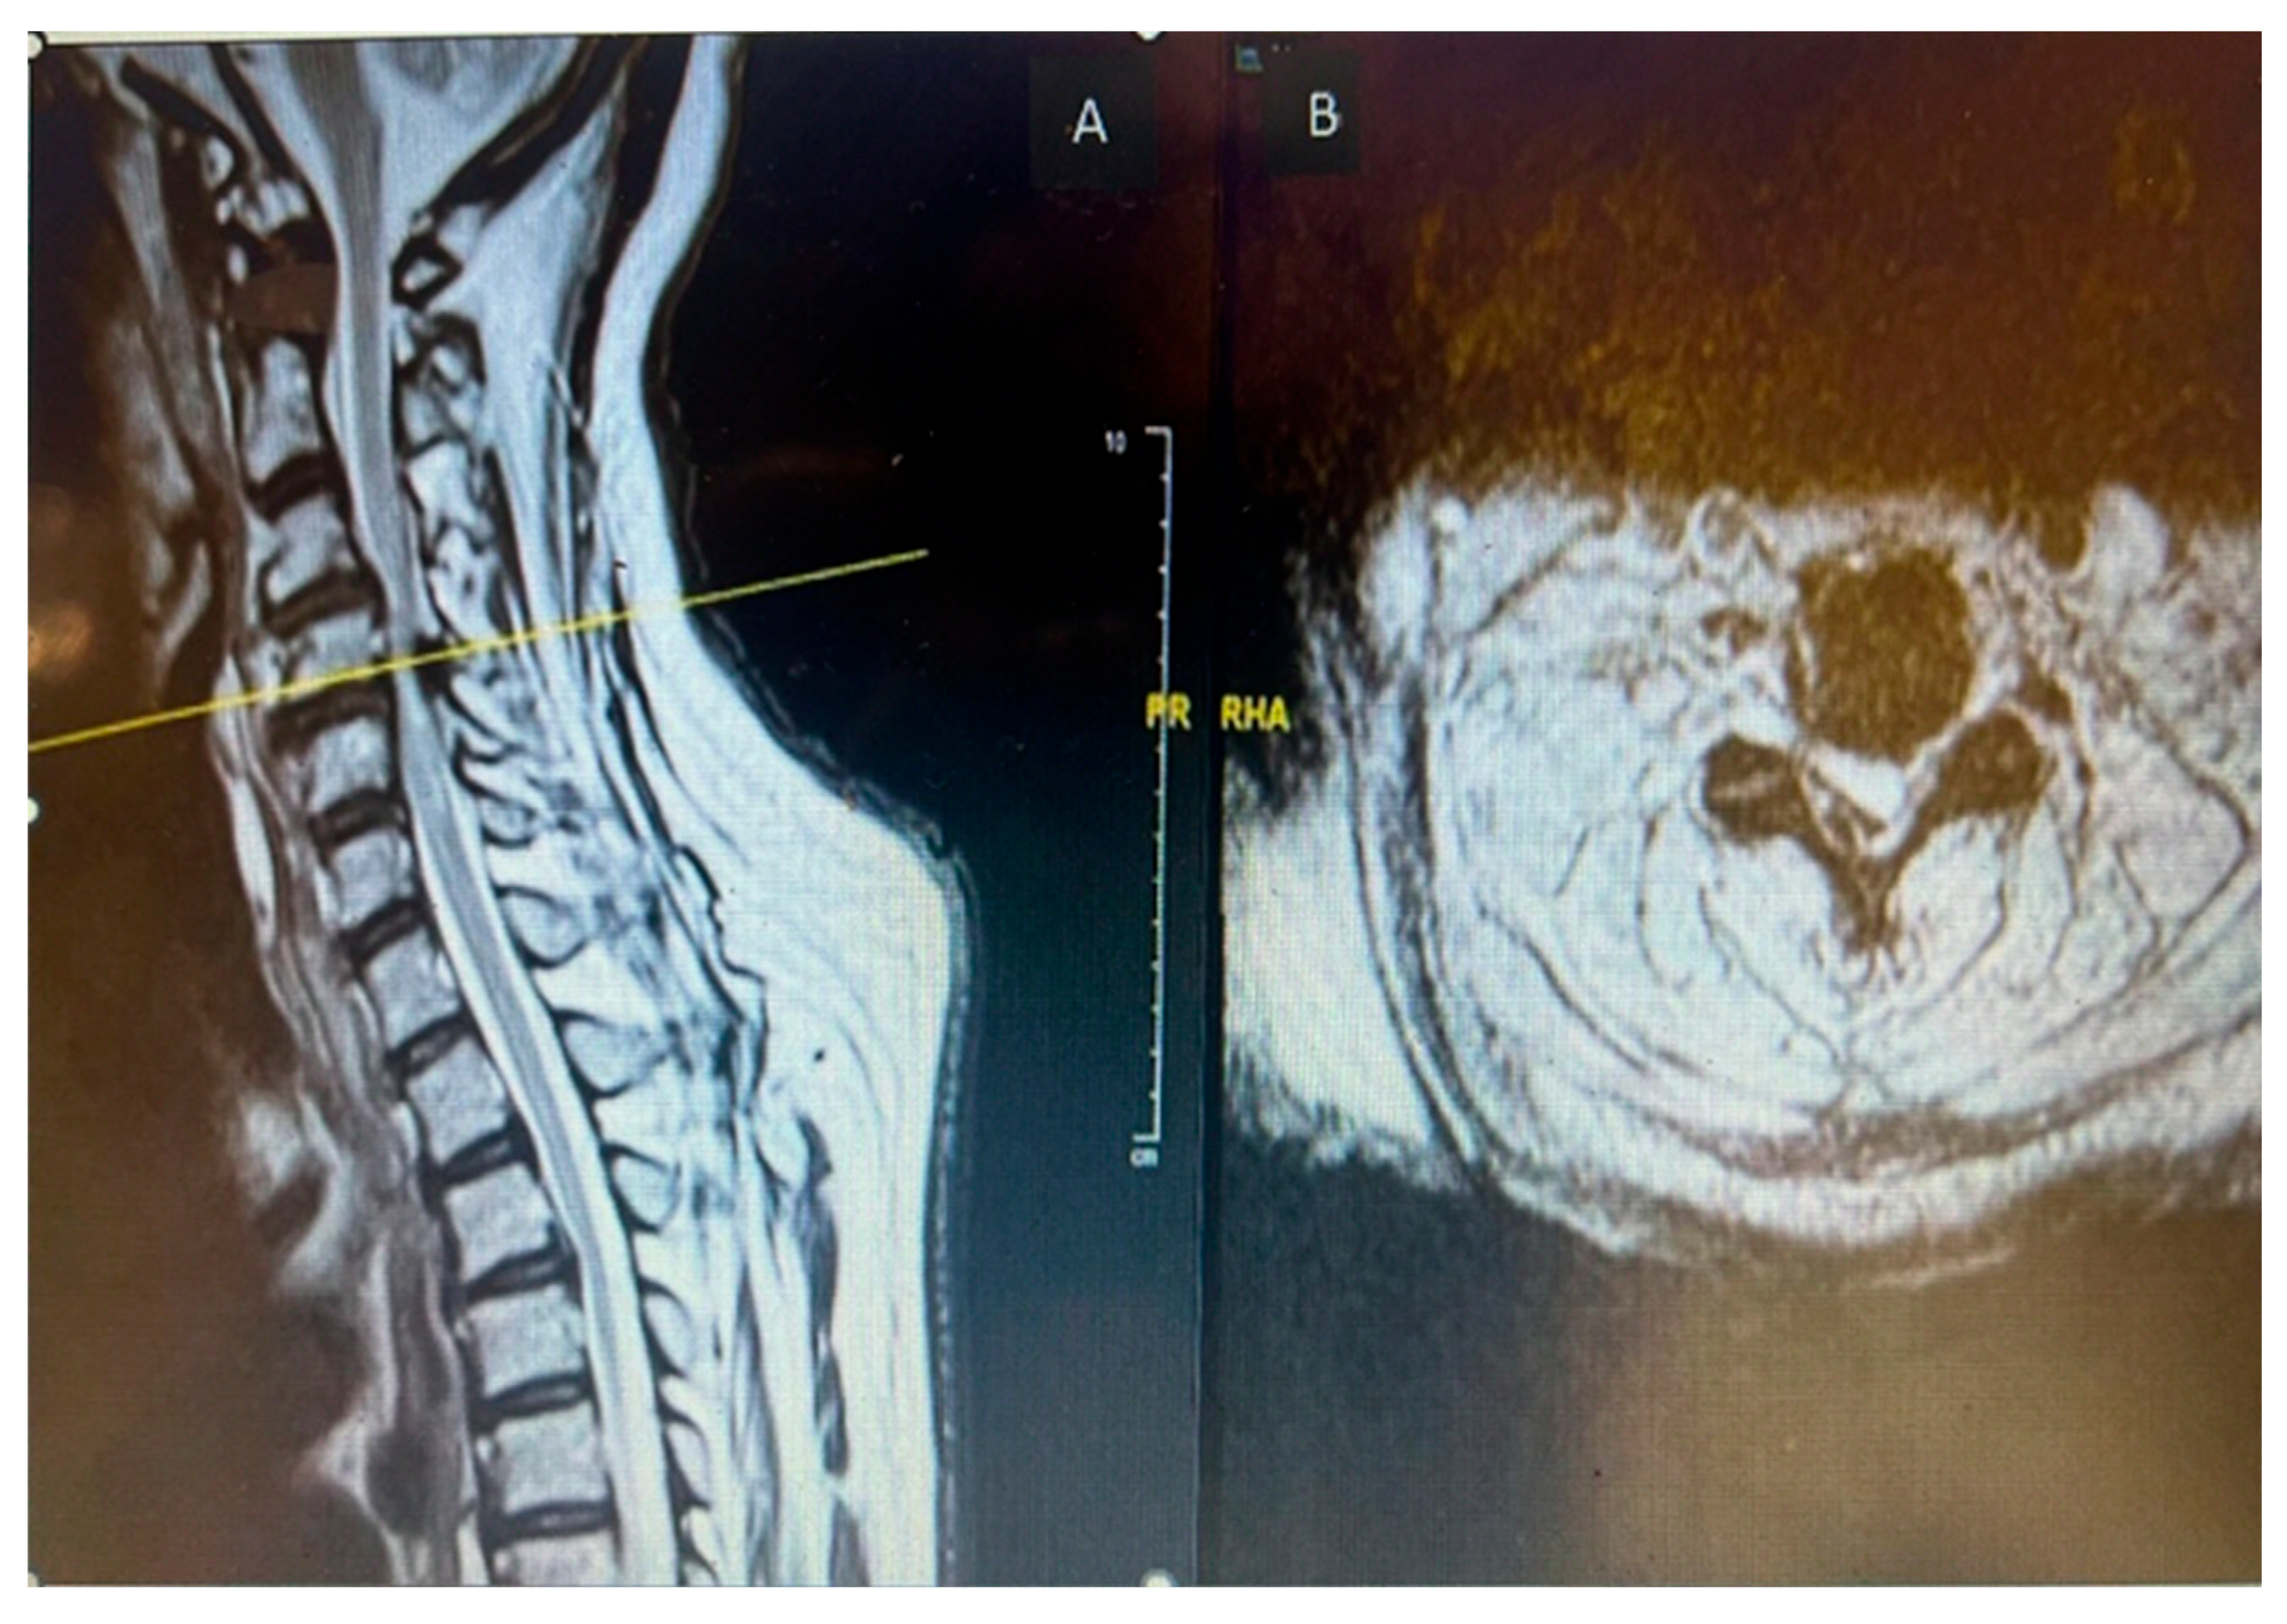

CT C Spine: Ossification of the right-side ligamentum flavum noted at C4/C5 and C5/C6 levels, with associated spinal canal narrowing, more severe at C4/C5.

Figure 1. Preoperative sagittal (A) and axial (B) CT cervical spine showing calcific deposit at the cervical 4 level causing spinal stenosis.

MRI Whole Spine: Severe central canal narrowing causing compression of the spinal cord with myelomalacia at C4/C5 level, with mild retrolisthesis at C4 over C5, thickening of the posterior longitudinal ligament, and ligamentum flavum hypertrophy. Various degrees of central canal narrowing and neural foraminal narrowing were noted at C3/C4, C4/C5, C5/C6, and C6/C7 levels, with additional findings including a small synovial cyst at C6/C7.

Figure 2. Preoperative MRI cervical spine T2 weighted sagittal (A) and axial (B) showing cord compression posteriorly with cord signal change at cervical 4 level.